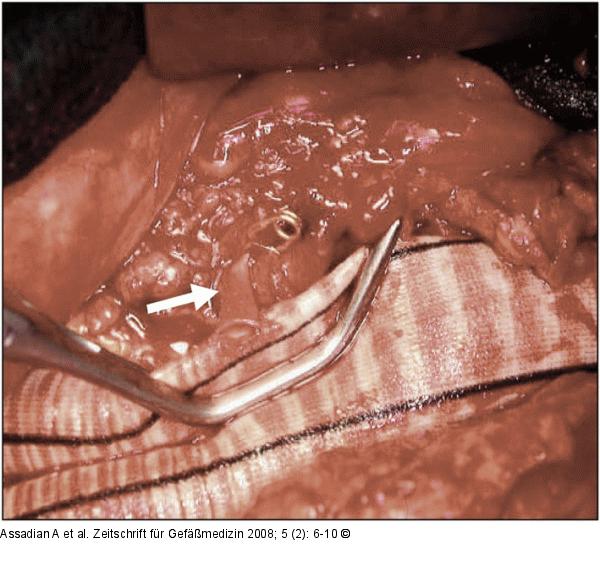

Abbildung 5: Bifurkationsprothese

Tangentiale Klemmung der Bifurkationsprothese zur Replantation derA. mensenterica inferior (weißer Pfeil) bei verschlossenen A. iliacae internae. |